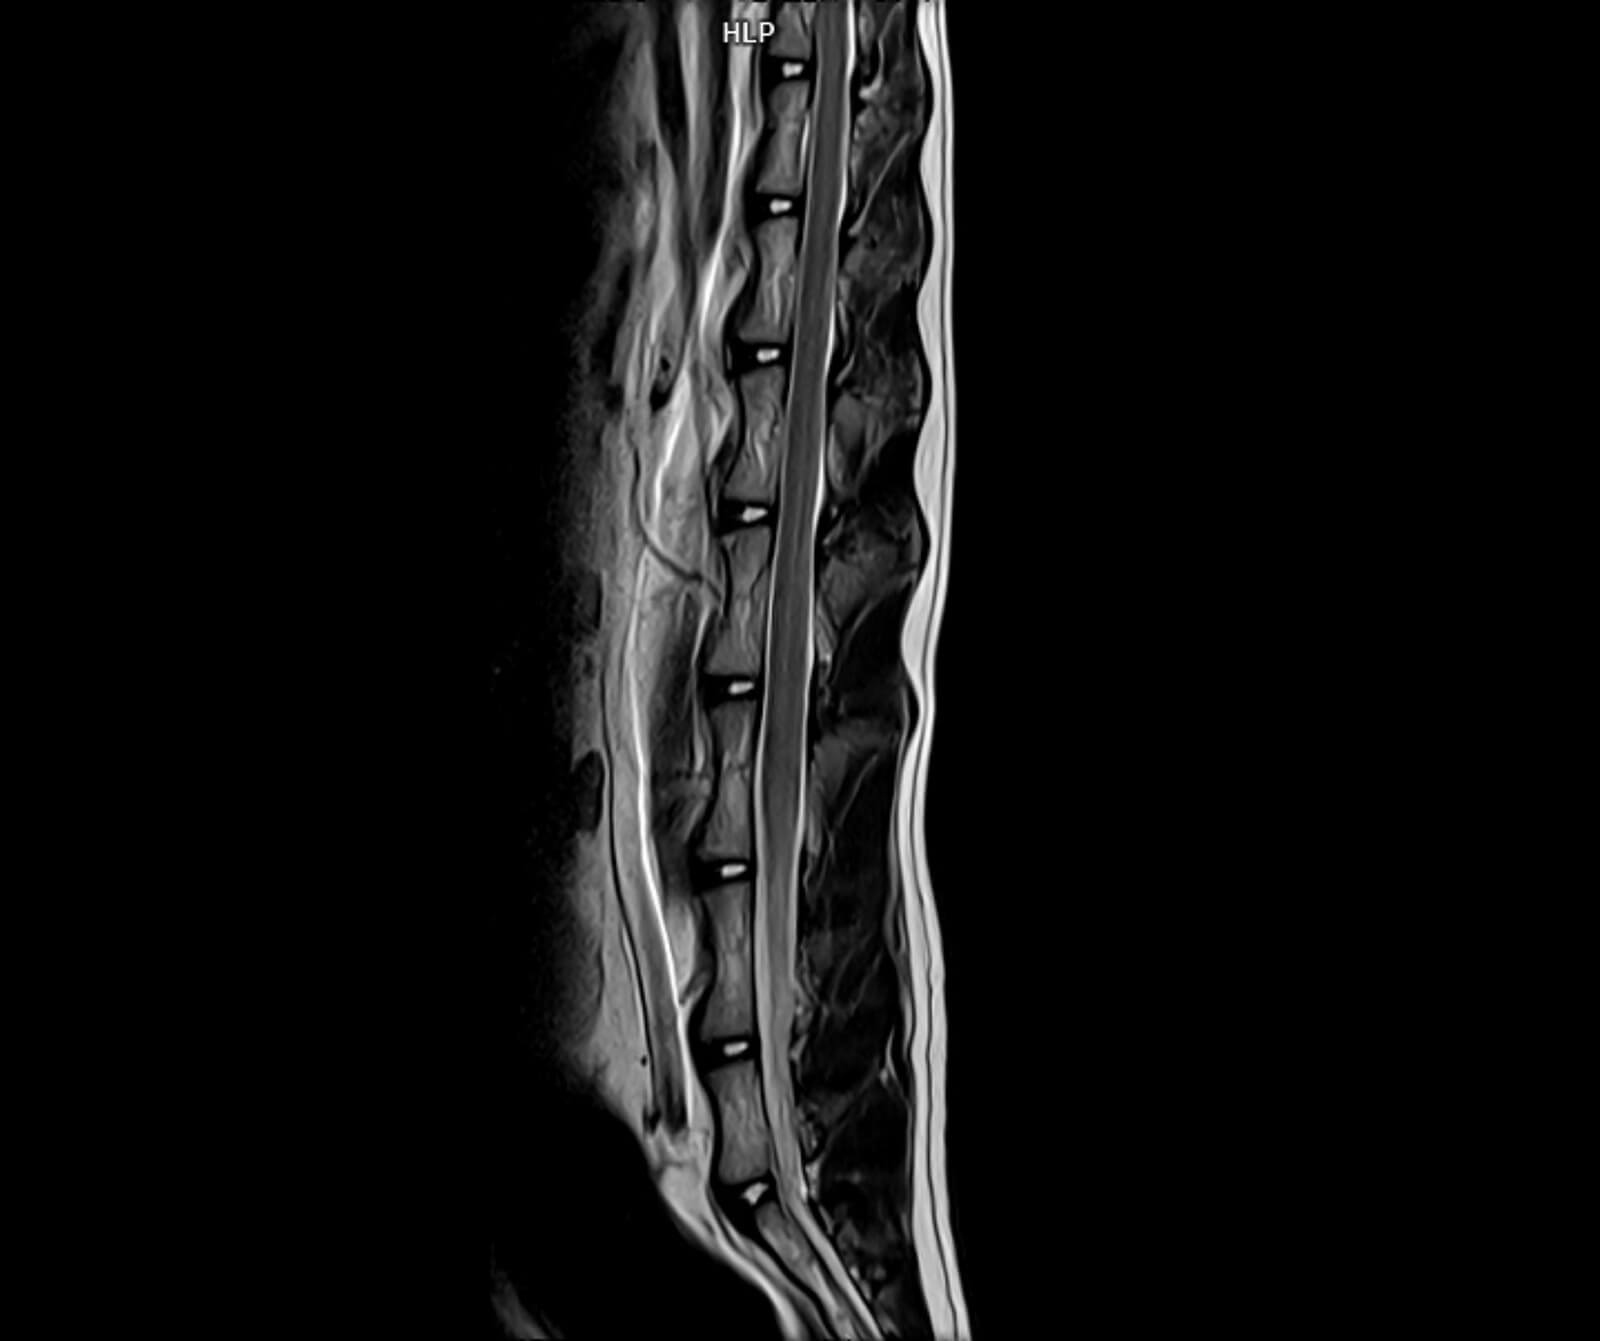

Veteriner hekimliğinde MR; beyin, omurilik, sinir sistemi, kas-iskelet sistemi ve iç organ hastalıklarının değerlendirilmesinde kritik rol oynar. Kemik yapılar dâhil olmak üzere vücudun tüm bölgeleri MR ile ayrıntılı şekilde incelenebilir.

• Omurga ve disk hastalıkları

• Disk hernisi, omurga tümörleri, enfeksiyonlar ve spinal stenoz

• Omurilikte travmatik ve dejeneratif değişiklikler